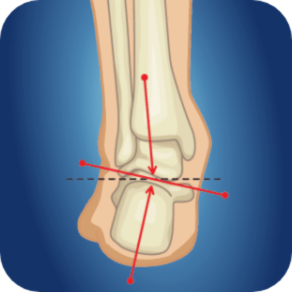

跟腱炎

跟腱炎最常见于30-40岁的人群,90%的病例发生在运动/锻炼期间。最常见的原因是过度的体能训练(尤其是跑步或俯卧撑)或在训练中穿着不合适的鞋子。